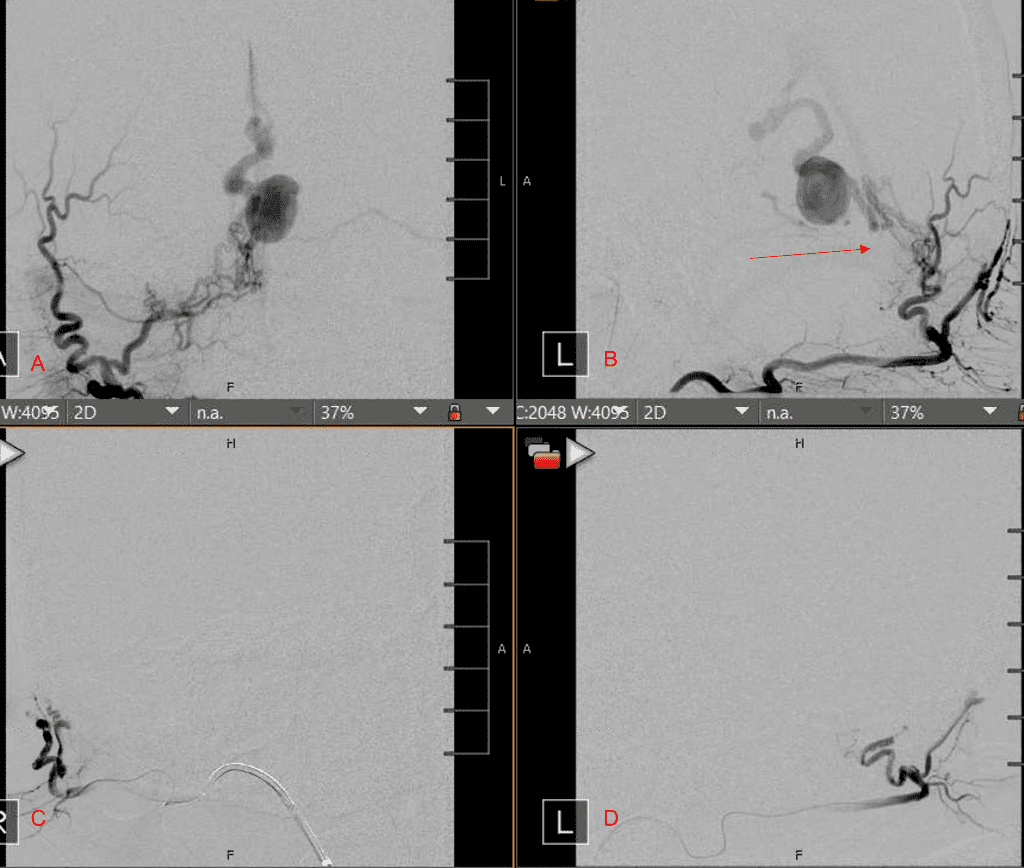

Figure 2. [A] Ruptured Varix/Aneurysm of the Deep Venous Posterior Fossa drainage and AV shunting (arrows) [B] Posterior Meningeal Artery Fistula [C] Right Middle Meningeal Artery Fistula [D] Post embolization Left Vertebral Angiogram demonstrates resolution of the high flow and pressure A-V Shunting following successful embolization with liquid embolic (NBCA).